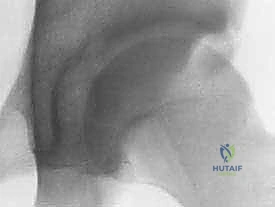

2. انحشار الكماشة (Pincer Impingement)

في هذا النوع، تكون المشكلة في التجويف (الحُق) نفسه. يمتد العظم البارز من الحُق ليغطي مساحة أكبر من الطبيعي من رأس عظم الفخذ. نتيجة لذلك، يتم "قرص" الشفا الحقي بين حافة التجويف وعنق عظم الفخذ عند ثني الورك. يُعد هذا النوع أكثر شيوعاً بين النساء في منتصف العمر.

* إذا كان من نوع "الكماشة"، يتم تشذيب حافة الحُق الزائدة.